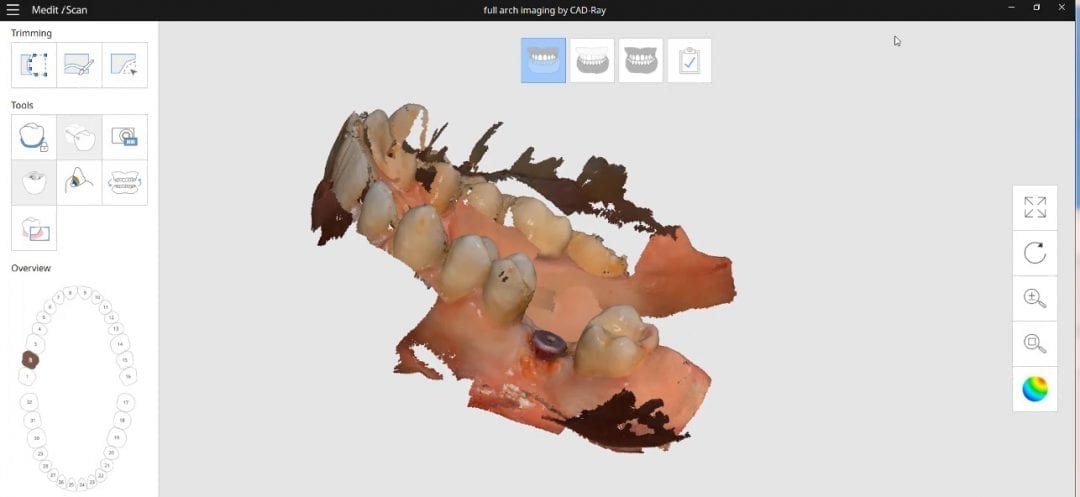

Checking Occlusion with Digital and Clinical Landmarks for a Clear Aligner Case

August 15, 2018Here’s a clear aligner case where the upper and lower arches were scanned and the buccal bite was taken with the Medit i500 IOS system. Prior to the digital impressions, […]